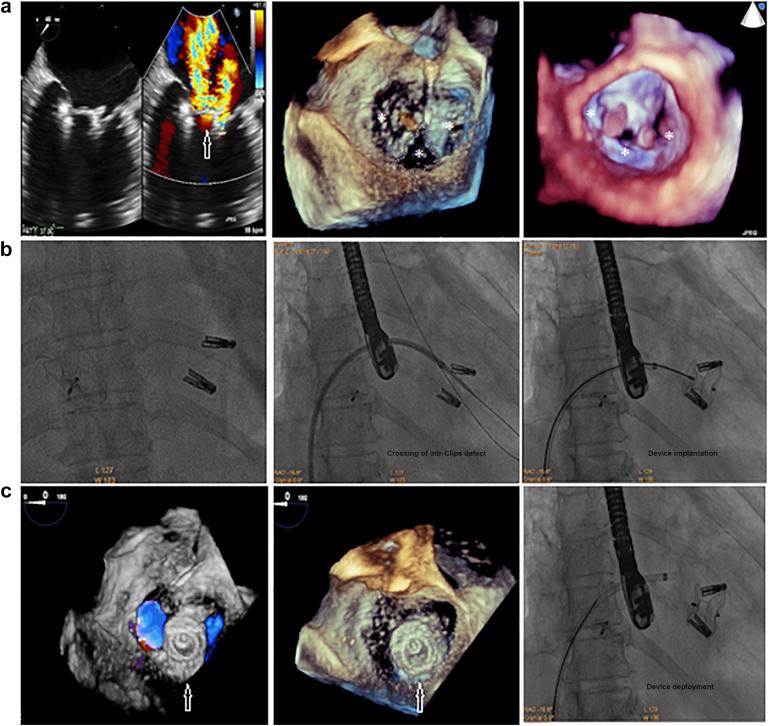

The study enrolled 16 patients; 9 (56.25%) with MVL perforations and 7 (43.75%) with post-MitraClip (Abbott Laboratories, Abbott Park, Illinois) residual MR, with a mean age of 55.75 ± 16.69 years. Mean perforation/jet diameters were 5.75 ± 1.67 and 6.5 ± 1.93 mm, and the mean 3D-vena contracta area was 0.54 ± 0.14 cm. Perforations were crossed retrograde (transaortic in 7 [43.75%] patients and transapical in 2 [12.5%] patients), and post-MitraClip devices residual jets were crossed antegrade (transvenous/transseptal). Six (37.5%) patients required arteriovenous loop formation for device deployment, that was antegrade transvenous/transseptal in 13 (81.25%) patients and retrograde transapical in 3 (18.75%) patients. Devices used were Amplatzer-ASO in 10 (62.5%) patients and Amplatzer-VP-II in 6 (37.5%) patients. Mean procedural and fluoroscopy times were 55.13 ± 16.24 and 16.25 ± 4.03 ​minutes, respectively. Patients passed successfully, without MV gradient change or device-related complications.

本研究共纳入16例患者;9例(56.25%)为MVL穿孔,7例(43.75%)为MitraClip(雅培实验室,伊利诺伊州雅培公园)夹闭术后残留MR,平均年龄为55.75±16.69岁。穿孔/射流平均直径分别为5.75±1.67和6.5±1.93mm,平均三维缩流颈面积为0.54±0.14cm²。穿孔采用逆行穿过(7例[43.75%]经主动脉,2例[12.5%]经心尖),MitraClip装置术后残留射流采用顺行穿过(经静脉/经房间隔)。6例(37.5%)患者需要形成动静脉环以部署装置,其中13例(81.25%)患者采用顺行经静脉/经房间隔,3例(18.75%)患者采用逆行经心尖。使用的装置为10例(62.5%)患者使用Amplatzer-ASO,6例(37.5%)患者使用Amplatzer-VP-II。平均手术时间和透视时间分别为55.13±16.24分钟和16.25±4.03分钟。患者均顺利通过,未出现MV梯度变化或与装置相关的并发症。